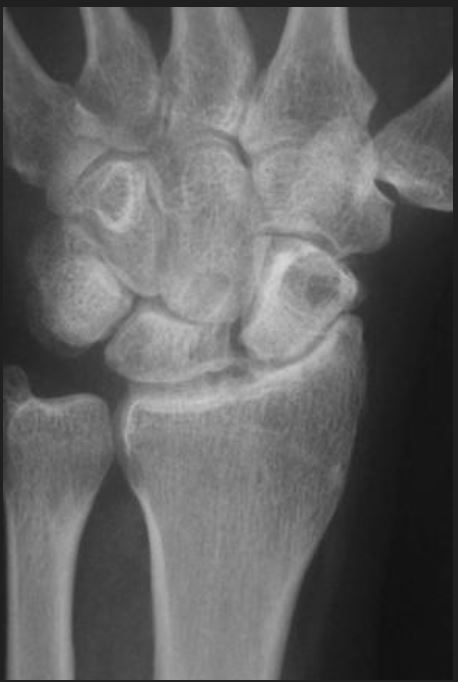

1. This is an AP radiograph of the right wrist demonstrating SNAC wrist (Scaphoid shape indicating loss of bone stock, reduced radiocarpal joint with osteophytes, arthrosis also noted between scaphoid and capitate) with preservation of the capitolunate joint and lunate facet.

2. SNAC- Stage 2 ( arthrosis of radioscaphoid joint & scaphocapitate joint, but preserved capitolunate joint)

DDX: SLAC

1. Proximal Row Carpectomy (PRC)

• Salvage, motion-preserving procedure, involves removal of proximal carpal row (scaphoid, lunate, triquetrum), articulation left is between proximal capitate and lunate.

• Requirement for success of PRC

– preserved cartilage of head of capitate.

• intact radioscaphocapitate ligament (RSC) (most volar radial ligament)

• Stability of the carpus after a PRC is dependent on preservation of the RSC ligament.